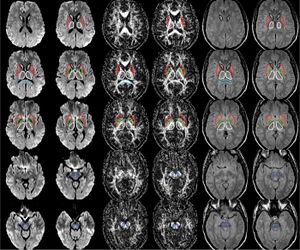

The regions-of-interest (ROIs) were manually drawn by an experienced radiologist by using the b 1000 images, averaged for all measured directions, the FA maps and the proton-density weighted images. For that purpose, the maps of ADC, FA, R2 and R2* as well as the proton-density weighted images were first co-registered. The ROIs were segmented by syncing the b 1000 images, averaged for all measured directions, the FA maps and the proton-density weighted images in ImageJ. The ROIs were stored in the ROI manager and transferred to the co-registered maps. The segmented brain regions were highlighted in different colors: CN—black; PU—red; GP—green; TH—white; SN—blue; CC—cyan. The diffusion-weighted images, the R2 and R2*-weighted maps were transferred to the 3D Slicer software in order to co-register the R2 and the R2* maps as well as the MD and the FA maps |